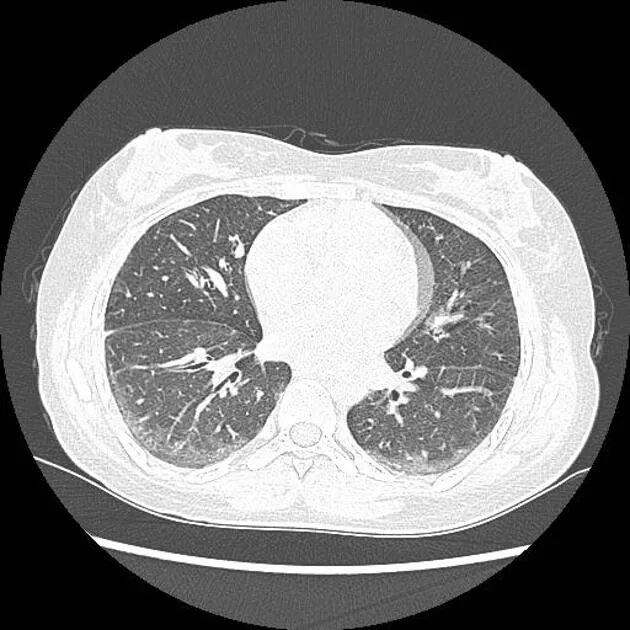

Гипостатические изменения кт